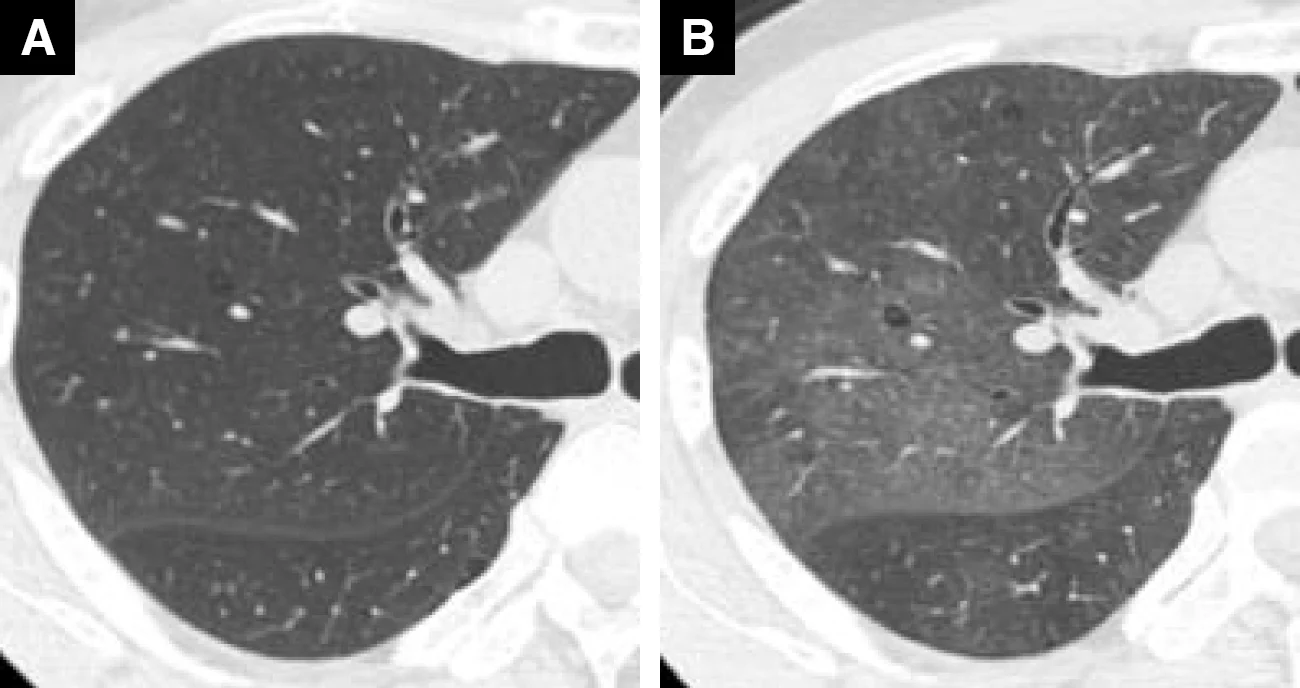

ドセタキセル投与症例(63歳、男性、乳がん)

A : 薬剤投与前 B : 薬剤投与後(紹介時)

Bでは極めて軽微ではあるが、両肺にすりガラス影を認めた

Bでは広範囲のすりガラス影がみられ、HP(過敏性肺炎)パターンと考えられた